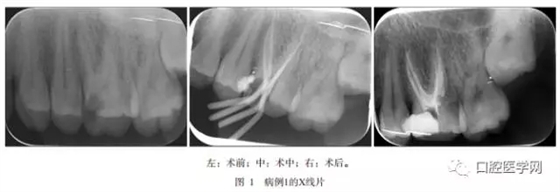

病例1,患者男,29歲,2013年3月因左上后牙冷熱刺激痛及夜間痛到青島市口腔醫(yī)院牙體牙髓科就診?;颊?周前曾出現(xiàn)自發(fā)痛和放射至顏面部疼痛。檢查:左側(cè)上頜第一磨牙近中深齲已露髓,探診疼痛,叩診無疼痛,冷診疼痛,持續(xù)數(shù)十秒。X線片示:左側(cè)上頜第一磨牙面及近中面大面積低密度影像與髓角相連,根尖區(qū)未見明顯低密度影像,腭側(cè)根根管影像模糊不清,似與二頰根對稱分布(圖1左)。

待無癥狀和根管無滲出后,Mtwo機(jī)用鎳鈦器械(VDW公司,德國)預(yù)備根管,25號0.6錐度主尖示尖(圖1中,圖2中),熱凝牙膠(KaVo公司,美國)行根管充填術(shù)。術(shù)后X線片示患牙根充恰填(圖1右,圖2右)。術(shù)后3個(gè)月復(fù)查,患者無任何不適,X線片顯示根尖區(qū)未有病變發(fā)生,治療效果佳。